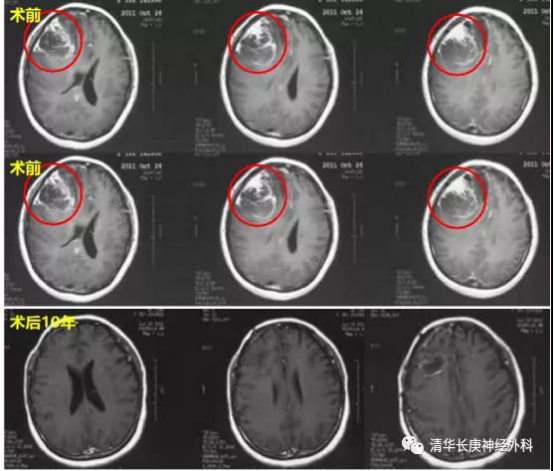

图3  手术前与术后10年磁共振随访

为了满足患者“最后的心愿”,杨学军主任为这位母亲制定了详细而周密的治疗计划。在高精尖的技术设备保障及强大的多学科诊疗团队协助下,2011年10月杨学军教授成功主刀完成手术,在病理明确为胶质母细胞瘤后便开始规范化的放化疗治疗,并在其后的紧密长期随访中开始了长程口服替莫唑胺治疗。在漫长而艰苦的肿瘤抗争过程中,故事的女主人公始终积极配合治疗,态度乐观,同时家人也给予了强大的精神支持。在手术住院心里压力最大的时候,患者丈夫每天都把孩子的视频带到医院。看着可爱的孩子,才最终支撑着度过了生命中最艰难的日子。

天若有情天亦老,也许这份母子深情打动了上天,这位母亲术后已经生存超过十年,实现了自己“听到孩子叫一声妈妈”的心愿。现在孩子已经十岁,病人创造了脑胶质母细胞瘤这一高度恶性肿瘤平均中位生存期不超过2年的生命奇迹,而且继续创造着新的记录!整个治疗过程中,杨学军教授团队为其进行了积极而规范的个体化综合治疗。目前,这位患者除了服药期间有轻度反应外,和正常人没有区别。病人也二次创业,在天津经营了一家非常有特色的披萨店,继续书写了人生新的篇章!